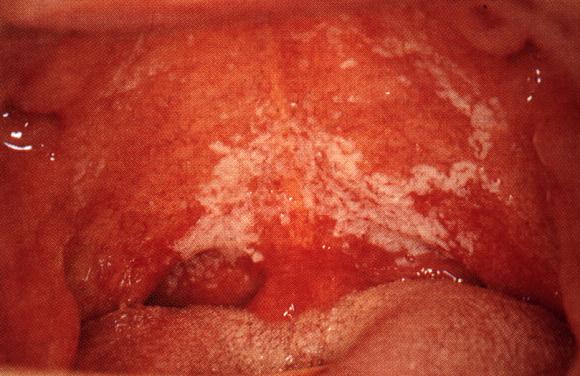

Suun sieni-infektio aiheuttaa usein limakalvojen polttelua, kipua ja arkuutta tai pahanhajuista hengitystä. Hammasproteesin käyttäjillä limakalvoalue proteesin alla on usein hyvin punainen. Myös suupielet saattavat olla arat ja punaiset.

Diagnoosi varmistetaan yleensä tekemällä hiivasoluviljely limakalvolta vanupuikolla otetusta sivelynäytteestä. Joskus diagnoosiin tarvitaan biopsia eli koepala, josta sieni-infektion lisäksi etsitään mahdollisia pahanlaatuisten solujen esiasteita.